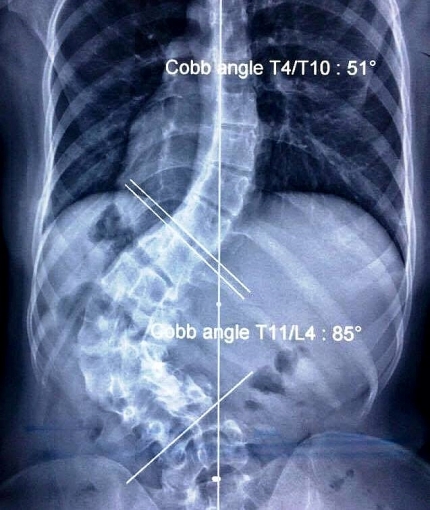

| Hình ảnh cột sống vẹo hơn 80 độ của bệnh nhân |

Theo PGS BS Võ Văn Thành, qua xem xét bệnh án, hình ảnh chụp chiếu, chẩn đoán bệnh nhân bị vẹo cột sống do sẹo co rút nặng hiếm gặp. Tới thời điểm hiện tại, Việt Nam chỉ mới ghi nhận 7 trường hợp mắc chứng bệnh này.